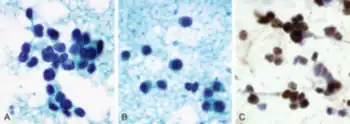

ARMS cells are often small with little cytoplasm. The nuclei of the cells are round with normal, dull, chromatin structures.[2] The ARMS cells often clump together and have fibrovascular septae that interrupts the aggregates. The fibrovascular septae that disrupts the aggregates often give the tumor the physiology of the alveoli found in the lungs.[2] In a few cases, there may not be any fibrovascular septae and this gives the tumor a more solid phenotype and no alveoli physiology.[2] Immunostaining for myogenin and for MyoD can be used to determine ARMS from other rhabdomyosarcoma tumors and immunostaining for AP2β and p-cadherin can distinguish fusion positive ARMS from fusion negative.[2]